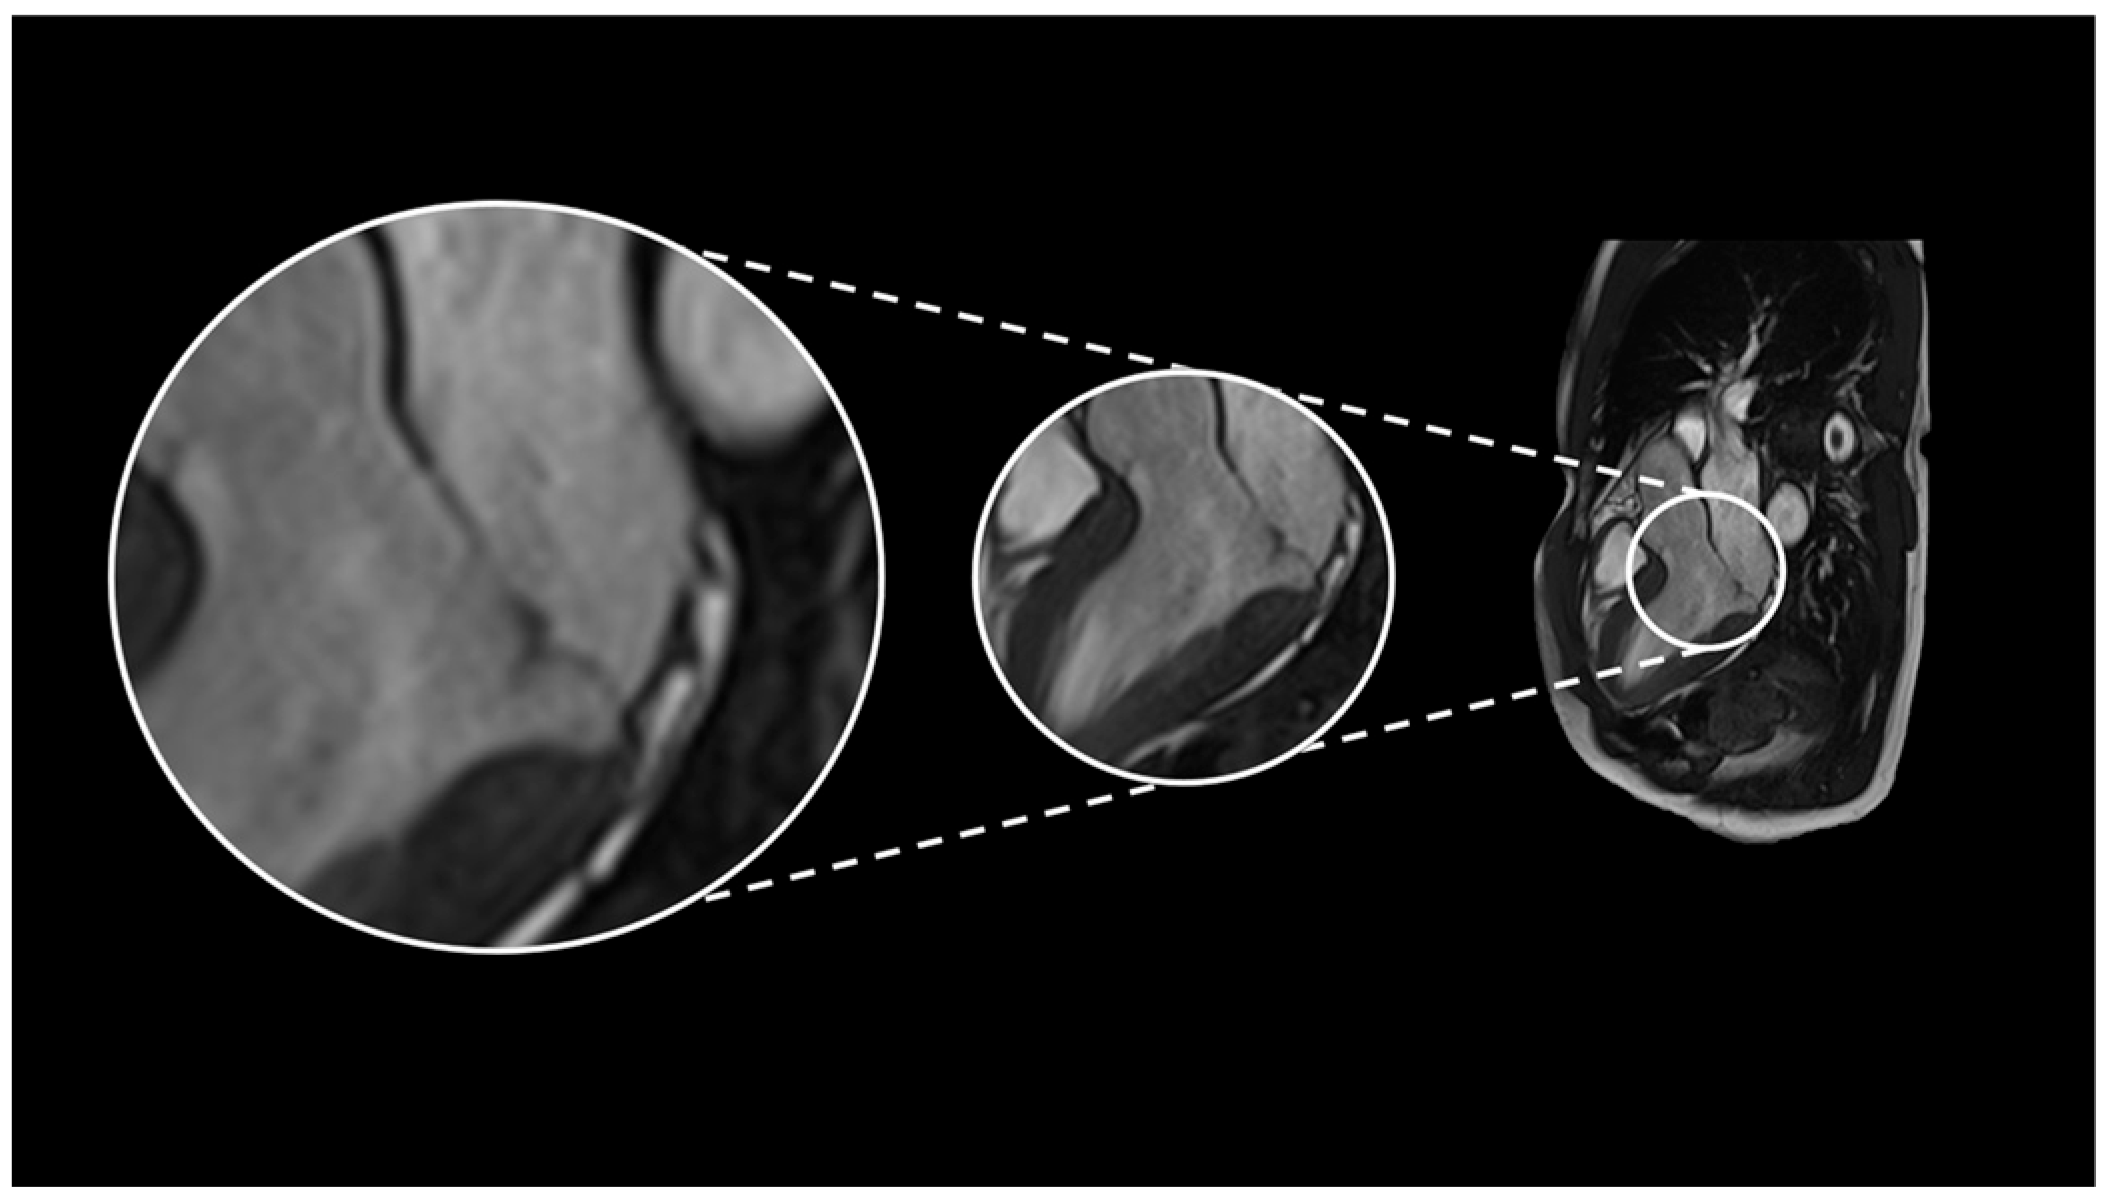

2.1. Case 1